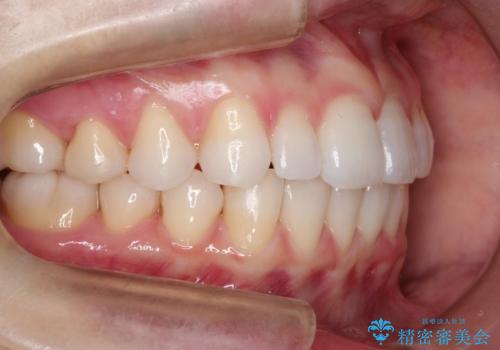

インビザラインで出っ歯を改善する 抜歯をしないinvisalign治療

- 非抜歯・遠心移動による前突の改善をマウスピースにて計画した。

非抜歯矯正の場合、大きく前歯を下げることはできませんが、奥歯の遠心移動や歯のサイズダウンにより歯軸を立て、見かけ上の出っ歯感をある程度改善することができます。